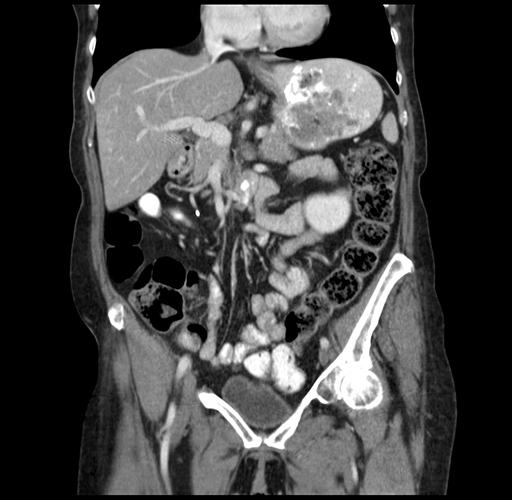

Coronal Venous